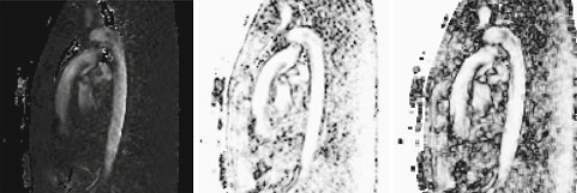

PURPOSE: Quantitative analysis of vascular blood flow, acquired by phase-contrast MRI, requires accurate segmentation of the vessel lumen. In clinical practice, 2D-cine velocity-encoded slices are inspected, and the lumen is segmented manually. However, segmentation of time-resolved volumetric blood-flow measurements is a tedious and time-consuming task requiring automation. METHODS: Automated segmentation of large thoracic arteries, based solely on the 3D-cine phase-contrast MRI (PC-MRI) blood-flow data, was done. An active surface model, which is fast and topologically stable, was used. The active surface model requires an initial surface, approximating the desired segmentation. A method to generate this surface was developed based on a voxel-wise temporal maximum of blood-flow velocities. The active surface model balances forces, based on the surface structure and image features derived from the blood-flow data. The segmentation results were validated using volunteer studies, including time-resolved 3D and 2D blood-flow data. The segmented surface was intersected with a velocity-encoded PC-MRI slice, resulting in a cross-sectional contour of the lumen. These cross-sections were compared to reference contours that were manually delineated on high-resolution 2D-cine slices. RESULTS: The automated approach closely approximates the manual blood-flow segmentations, with error distances on the order of the voxel size. The initial surface provides a close approximation of the desired luminal geometry. This improves the convergence time of the active surface and facilitates parametrization. CONCLUSIONS: An active surface approach for vessel lumen segmentation was developed, suitable for quantitative analysis of 3D-cine PC-MRI blood-flow data. As opposed to prior thresholding and level-set approaches, the active surface model is topologically stable. A method to generate an initial approximate surface was developed, and various features that influence the segmentation model were evaluated. The active surface segmentation results were shown to closely approximate manual segmentations.